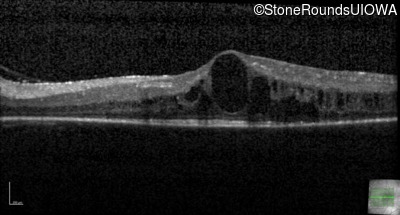

Optical Coherence Tomography - Right - 20/30 -2

Exemplar / OCT Stack